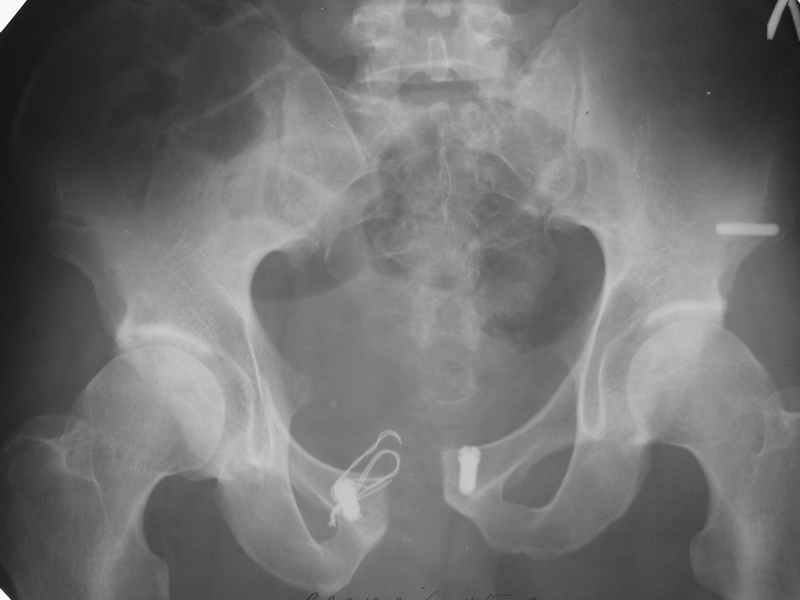

Что-то такое подразумевается? См. приложение...

Но IMHO считаю, что недостатком применения пластин в этой области является именно не физиологическая стабилизация, которая нередко приводит к перелому оных или расшатыванию винтов. Таких картинок ни у кого нет.

Александр Николаевич при всём моём глубоком уважении, несколько формальный подход. Серкляж разорван, так и на локтевых отростках рвут и на бедре пластины гнут, однажды даже видел погнутый аппарат Илизарова, но там д.т.п. было.